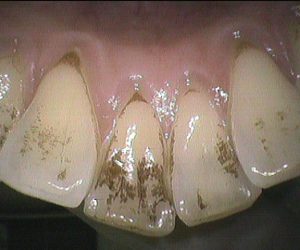

今日のクリーニングです🦷     下の前歯の表側、裏側のクリーニング前後のお写真です📸 歯と歯の間や歯ぐきのきわには歯石が付着していて、 歯の表面にはステイン(着色)が […]